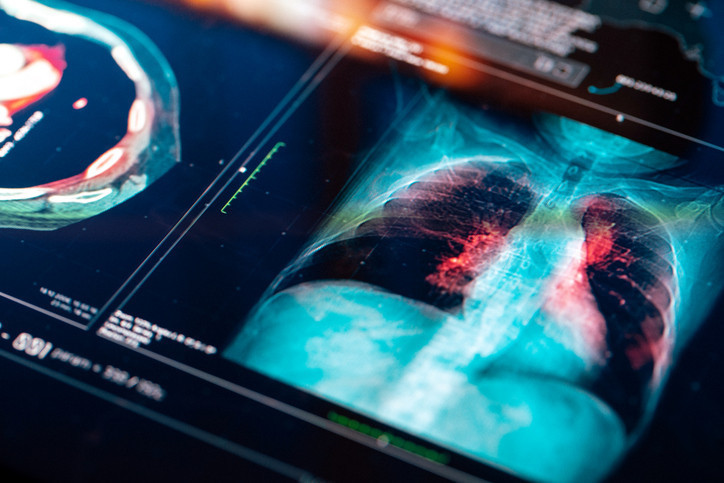

KOAH, hava kesecikleri olan bronşların daralması sonucu akciğerde elastikiyet kaybı, nefes darlığı, öksürük ve hava akımının kısıtlanması ile ortaya çıkan kronik inflamatuar bir akciğer hastalığıdır. KOAH, amfizem ve kronik obstrüktif bronşiti de içerir.

KOAH tüm vücut sistemini olumsuz etkileyen önemli bir hastalıktır. Akciğer yaşlanmasını hızlandırmaktadır. Diyabet, kemik erimesi, kalp damar tıkanıklıkları ve kaslarda enfeksiyon dışı iltihaplar gibi sorunlar KOAH ile birlikte görülebilmektedir.